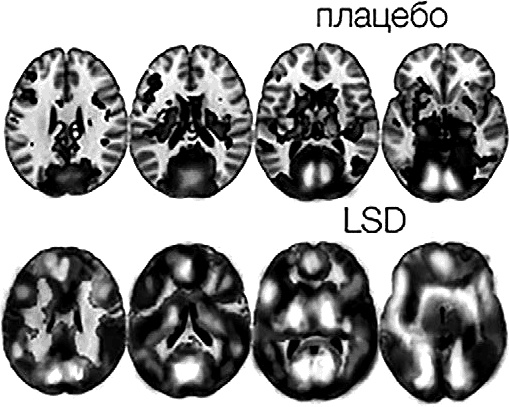

И поскольку лучше один раз увидеть, чем сто раз услышать, давайте просто посмотрим на рис. № 16.

Рис. № 16. Сравнение эффектов плацебо и LSD на фМРТ-срезах из исследования Имперского колледжа Лондона под эгидой Фонда Беркли

Почувствуйте, что называется, разницу.

Мозг человека, находящегося под воздействием LSD, претерпевает своеобразную рассинхронизацию. Если в обычной ситуации различные отделы мозга и нейронные сети включаются в нём последовательно (в соответствии с задачами и своей специализацией), то под влиянием LSD он вспыхивает весь, целиком.

В каком-то смысле мозг испытуемых напоминал неспециализированный ещё мозг младенца: мозг, в котором нет «я» и натренированной последовательности переключений между нейронными сетями (ДСМ, ЦИС, СВЗ).

Иными словами, перед нами работа целостного мозга, или, как говорят сами исследователи, – «унифицированный человеческий мозг».